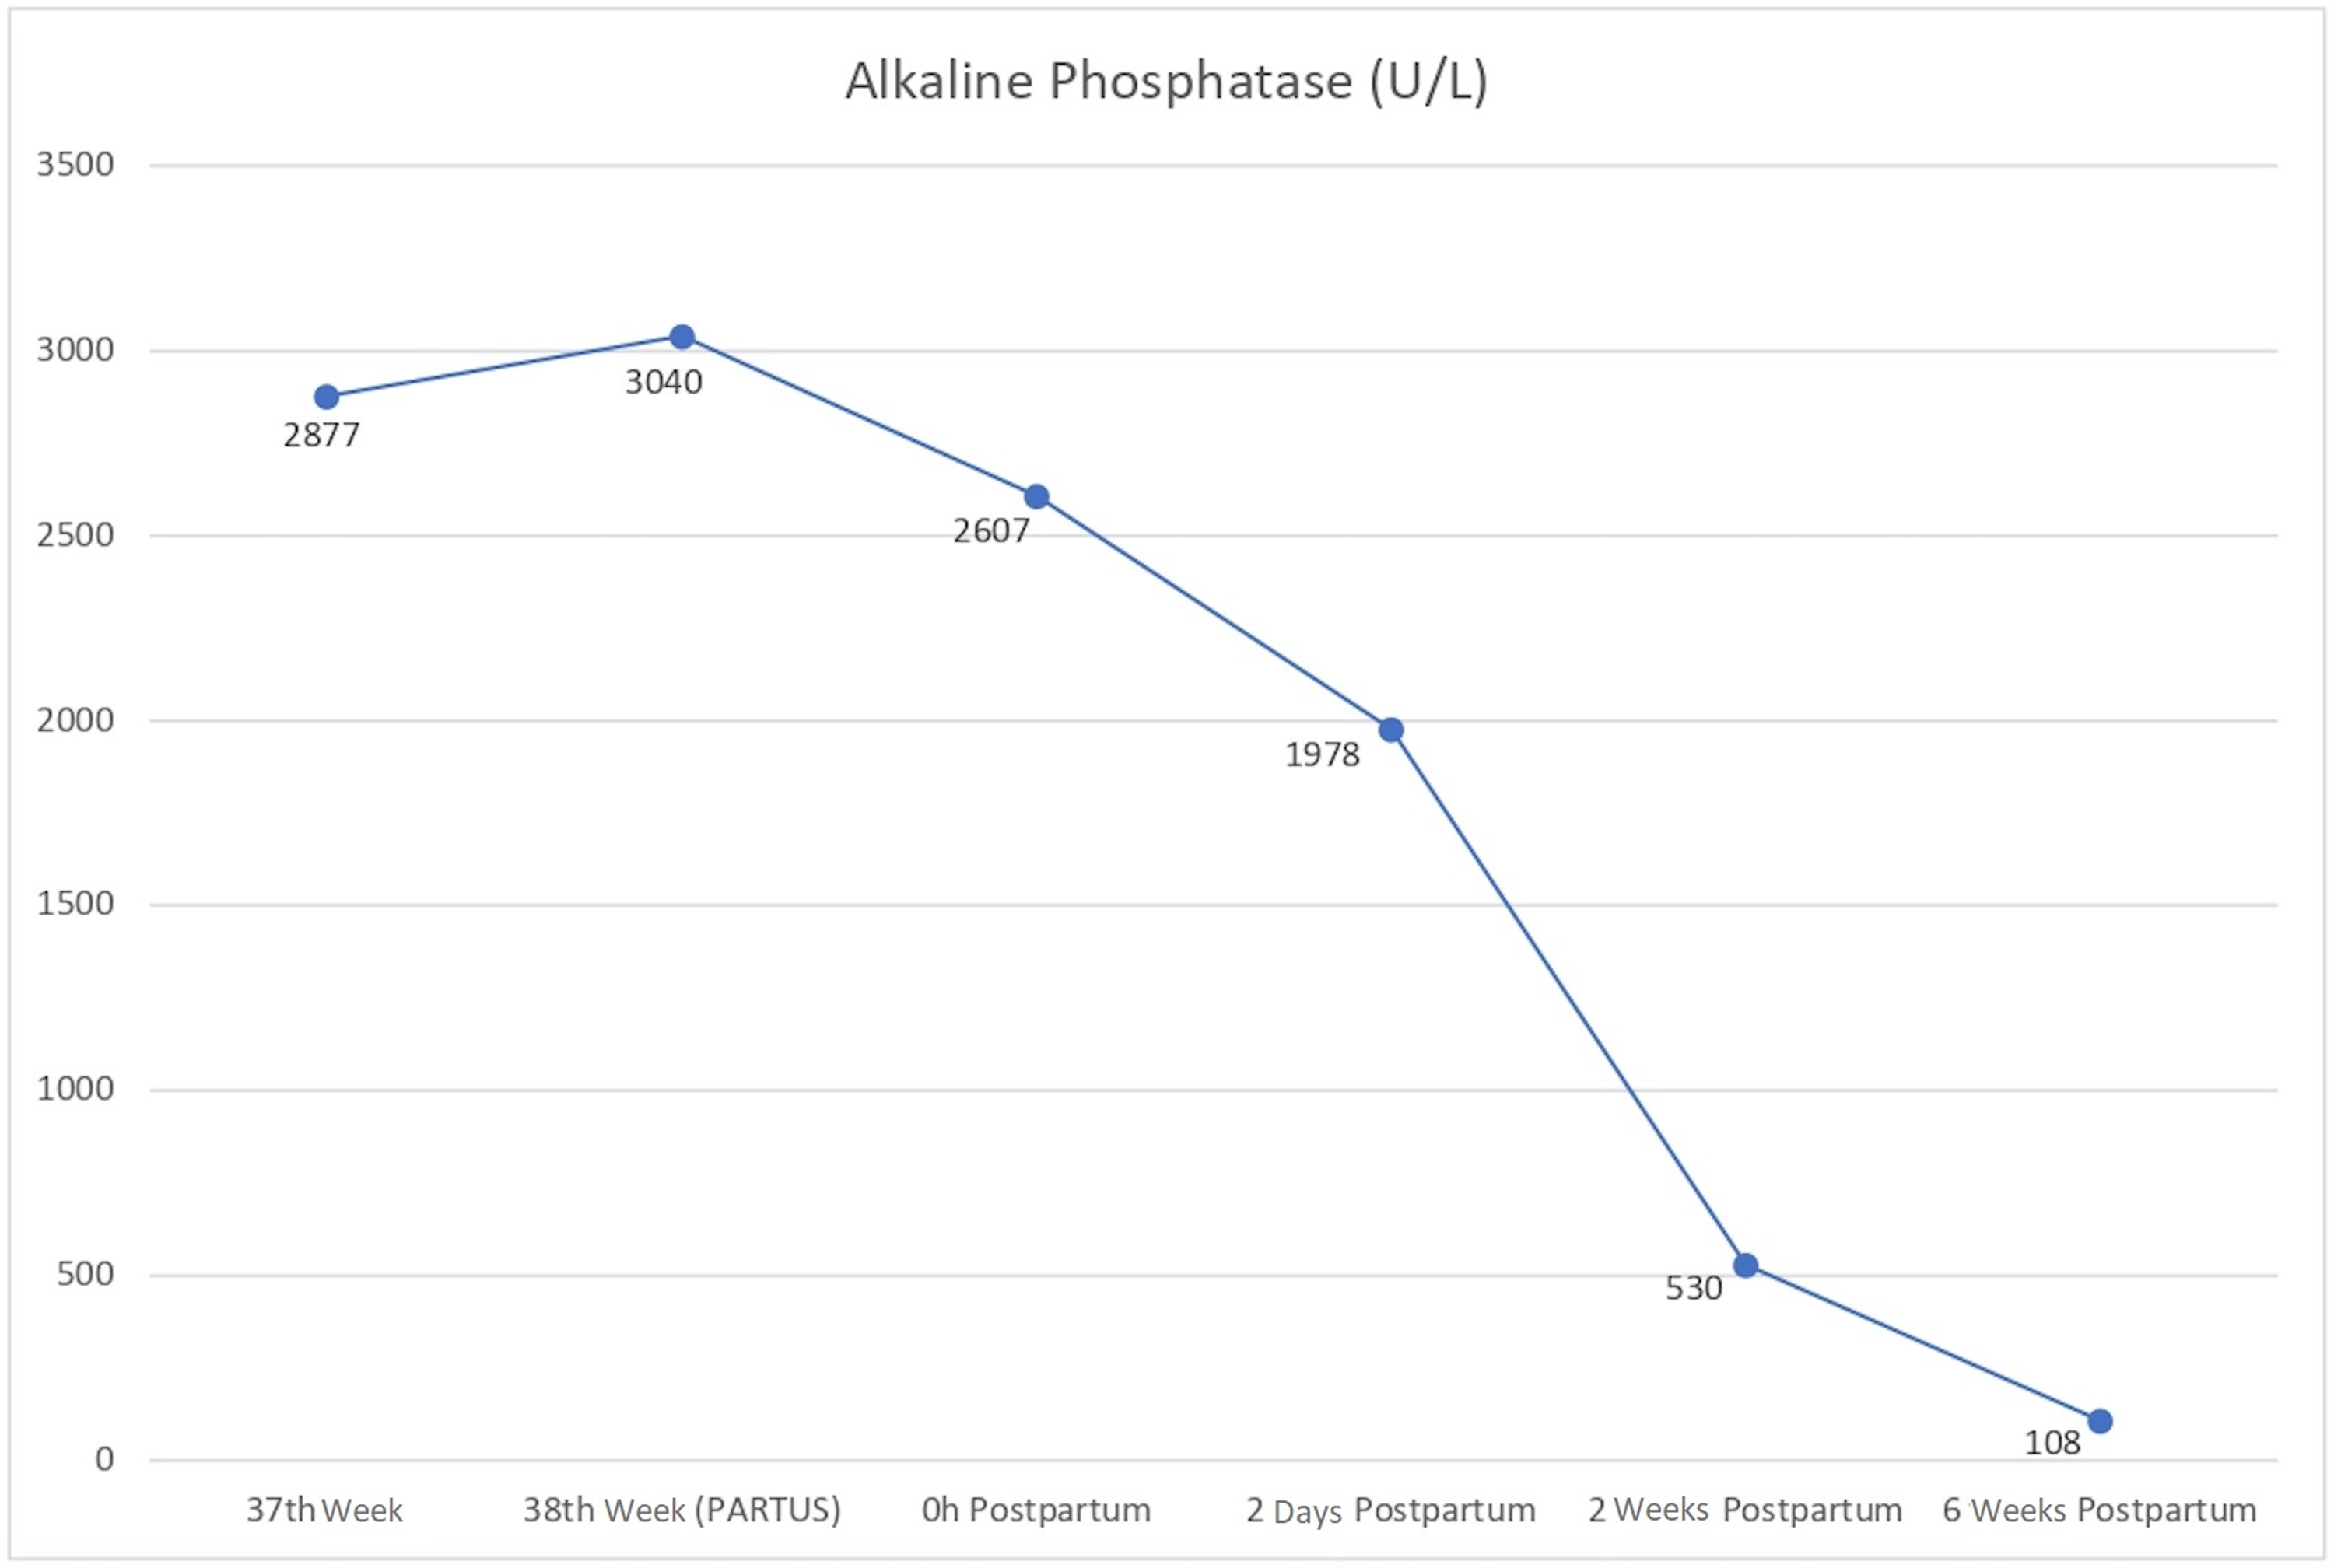

Improving Perinatal Care In The Rural Regions Worldwide By Wireless Enabled Antepartum Fetal Monitoring A Demonstration Project

Frontiers Thyroid Function In Preterm Low Birth Weight Infants Impact On Diagnosis And Management Of Thyroid Dysfunction